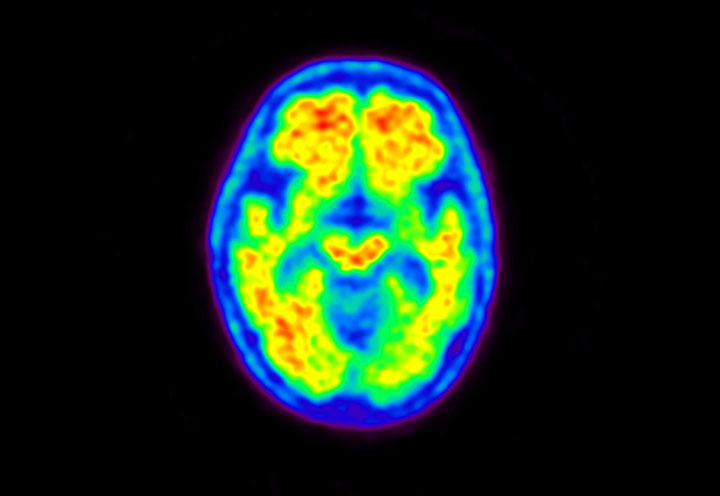

Head / Case5 : Amyloid

Courtesy : Kindai University Hospital

- Imaging protocol

- Injected dose: 4.27 MBq/kg, 18F-Flutemetamol

- Uptake time: 99 minutes

- Scan time: 20 minutes